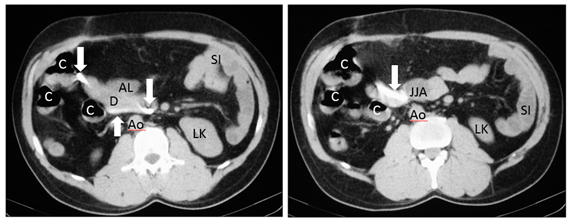

During the six years following laparoscopic cholecystectomy, the patient undergoes frequent medical examinations due to multiple episodes of acute cholangitis that require endoscopic dilatation of the stenosis and placement of biliary stents through endoscopic retrograde cholangiopancreatographies (ERCP) until, finally, the patient had a biliodigestive (Roux-en-Y) anastomosis. During surgery, the stent is not removed as it is not visualized and, based on the suspicion of a possible distal migration, a radiograph of the abdomen is requested, in which the prosthesis seems to be found in the hepatic angle of the colon (Figure 6). Over five months the patient was asymptomatic, and the stent, presumably in transit, was controlled through radiographs but it does not seem to change its location. In view of the above, it is decided to perform a computerized tomography to accurately locate the prosthesis (Figures 7-8), it was shown that it was located in the duodenum with the distal end in the region of the jejunal anatomy, since it had not managed to circumvent the angulation that occurs in the efferent jejunal loop just after the anastomosis.

Figure 8 Axial CT images showing the high density migrated stent (arrows), located in the duodenum (D) with end in the jejunonojejunal anastomosis (JJA). Jejunal afferent loop (AL), left kidney (LK), colon (C), small intestine (SI), aorta (Ao).